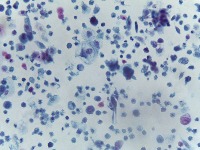

Medical Diagnostics: This model can be used in the healthcare industry to provide high-speed automated analysis of pathology slides, determining whether cells are normal or abnormal, and assisting in diagnosis of various diseases such as cancer.

Scientific Research: Researchers studying cell biology or genetics can use this AI model for their studies on cellular abnormalities and diseases. This can accelerate the onset of breakthroughs in medical science.

Pharmaceutical Applications: Pharmaceutical companies can use this model in drug discovery and development process. By identifying how different medications affect normal and abnormal cells, they can speed up and enhance their research.

Educational Tool: This AI model could serve as a rich educational tool in courses related to biology, medicine and health sciences, helping students to visualize and understand differences between normal and abnormal cells.

Personalized Medicine: This model can be used to analyze patients' cells to create personalized treatment plans. Understanding an individual's cellular structure could help healthcare professionals tailor treatments to the patient's specific needs.